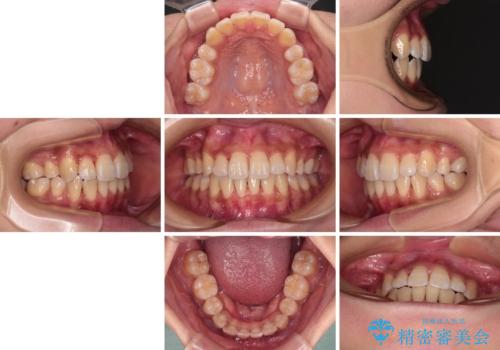

- 前歯のデコボコやクロスバイトと上顎の前突感による口の閉じにくさを気にして来院された患者様です。

目立たない装置を希望されたので、上顎が裏側装置のハーフリンガルを選択し、上下左右の小臼歯(計4歯)を抜歯して矯正治療を行うこととしました。

表側のワイヤー矯正に比べると治療期間は長く、費用も高額となりますが、どうしても目立たせたくないという方にはお勧めの抜歯矯正です。